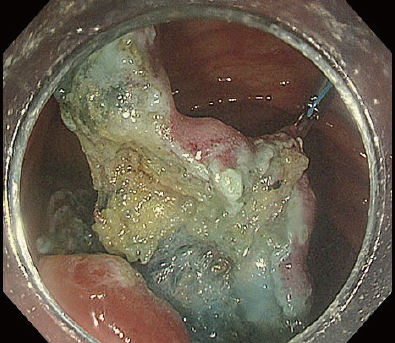

[Case 2] Descending colon IIc 25 mm

When fibrosis is present, introduction into the submucosal layer becomes even more difficult. This case has a higher degree of difficulty than Case 1. It is a IIc lesion near an anastomotic site of the descending colon after surgery, accompanied by severe cramping and depression (Fig. 8).

In this case, introduction into the submucosal layer appears more difficult than usual because the mucosa is thickened due to inflammation. We therefore applied the WPM². This technique was originally proposed for duodenal ESD but can be a powerful tool when introduction into the submucosal layer is difficult. As shown in Fig. 9, it effectively visualizes the tissue to be cut by properly using the tapered hood. Because immersion expands the visual field, the knob-shaped tip of DualKnife J can be precisely applied to the point to be cut, enabling truly precise ESD.

Once the DualKnife J has been introduced into the submucosal layer, you can use the PCM to excavate the central part and expose the fibrotic region (Fig. 9). After that, you can spread the pocket in the usual way and complete en-bloc resection.